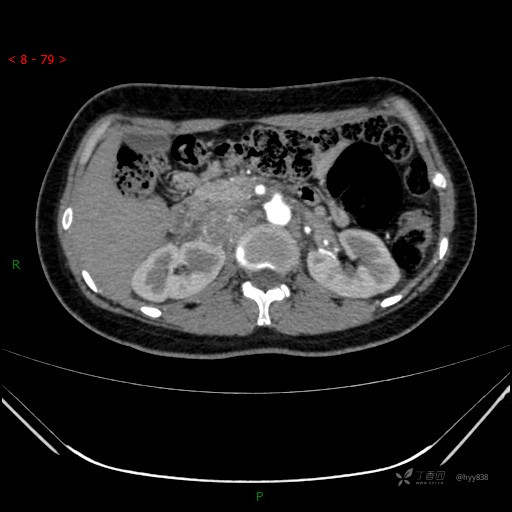

肾上腺CT平扫

动脉期

静脉期